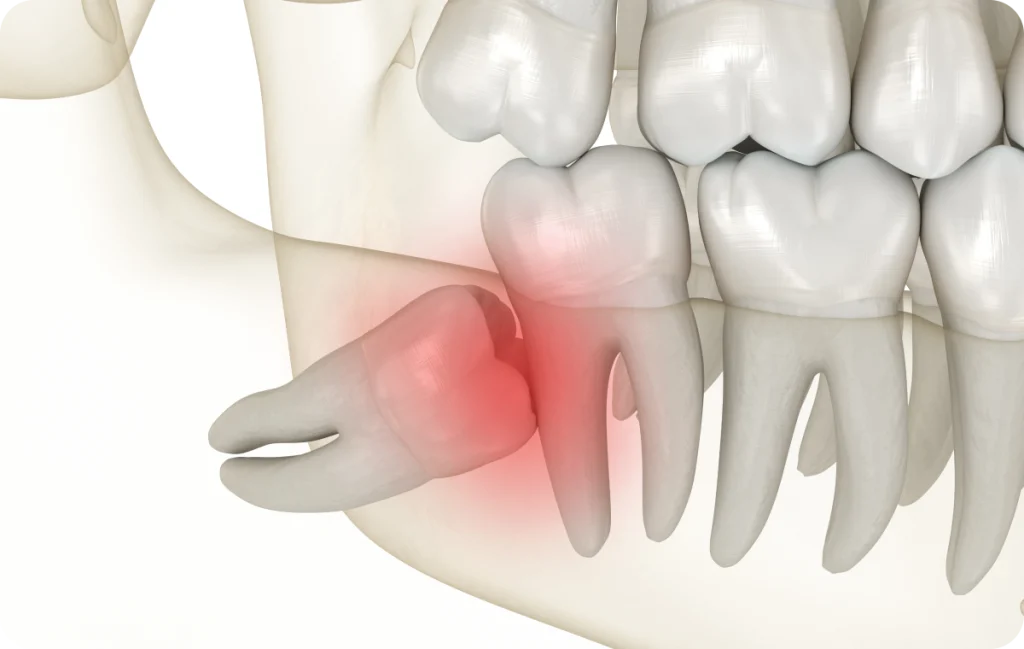

Le manque de place constitue l’une des situations les plus courantes. Lorsque l’arcade dentaire est déjà complète, l’arrivée des dents de sagesse peut être compromise. Elles peuvent alors pousser de manière inclinée ou rester bloquées sous la gencive.

Cette configuration peut rendre le nettoyage difficile et favoriser l’apparition d’inflammations locales. Une évaluation permet de déterminer si une surveillance simple est suffisante ou si une prise en charge doit être envisagée.

- Dents de sagesse partiellement sorties

Lorsqu’une dent de sagesse n’émerge que partiellement, une zone de gencive peut rester en recouvrement. Cette situation favorise l’accumulation de résidus alimentaires et de bactéries.

Une inflammation locale peut alors apparaître, accompagnée de douleurs ou d’une gêne lors de la mastication. Une attention particulière à l’hygiène et un suivi adapté permettent de limiter ces désagréments.

- Dents de sagesse incluses

Une dent de sagesse incluse reste entièrement ou partiellement enfermée dans l’os de la mâchoire. Cette situation peut rester asymptomatique pendant longtemps. Toutefois, une dent incluse peut parfois exercer une pression sur les dents voisines ou être associée à des modifications des tissus environnants.